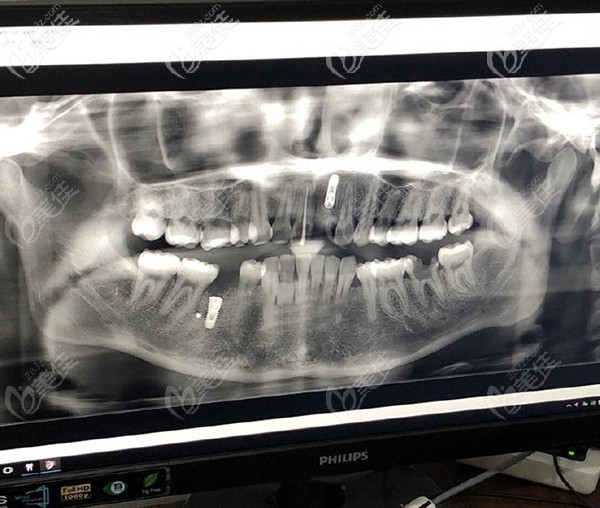

問題是本寶寶還不止缺一顆牙,只不過在我看來門牙尤為重要,來院后,醫(yī)生大概看了牙齒情況后,建議還是拍個CT看看,以便于確認(rèn)給我更好的方案。

放大看看更清楚

【牙齒情況】:門牙缺失一顆,下半口缺失一顆,但是有殘根。